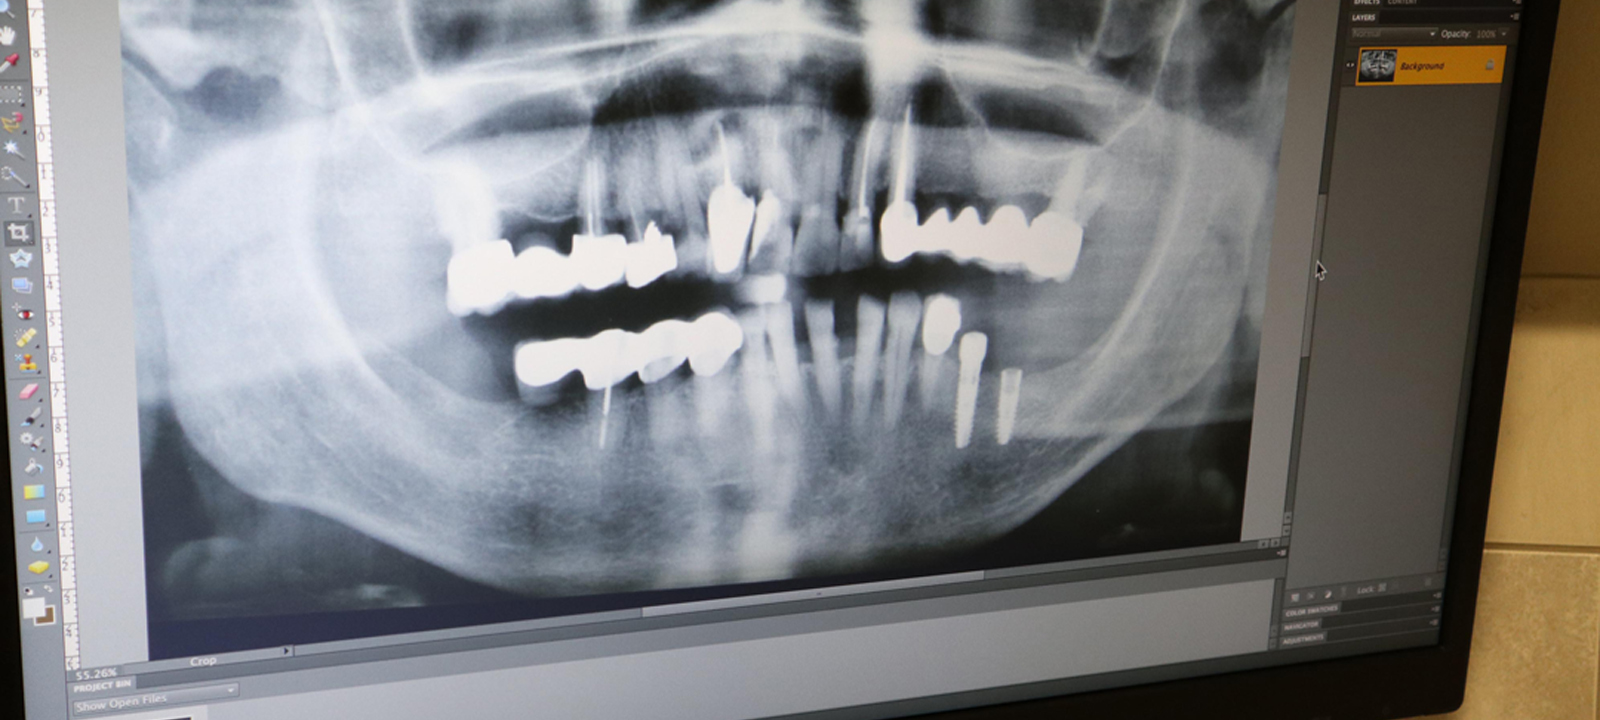

Στην καθημερινή οδοντιατρική πρακτική, η ακτινογραφία αποτελεί ένα βασικό διαγνωστικό μέσο. Με τη χρήση ακτινογραφικού μηχανήματος τελευταίας τεχνολογίας, μειωμένης έκλυσης ακτινοβολίας, κατάλληλου και για παιδιά, βγάζω ακτινογραφίες υψηλής ποιότητας, με δυνατότητα ψηφιακής προβολής σε υπερύψηλη ανάλυση.